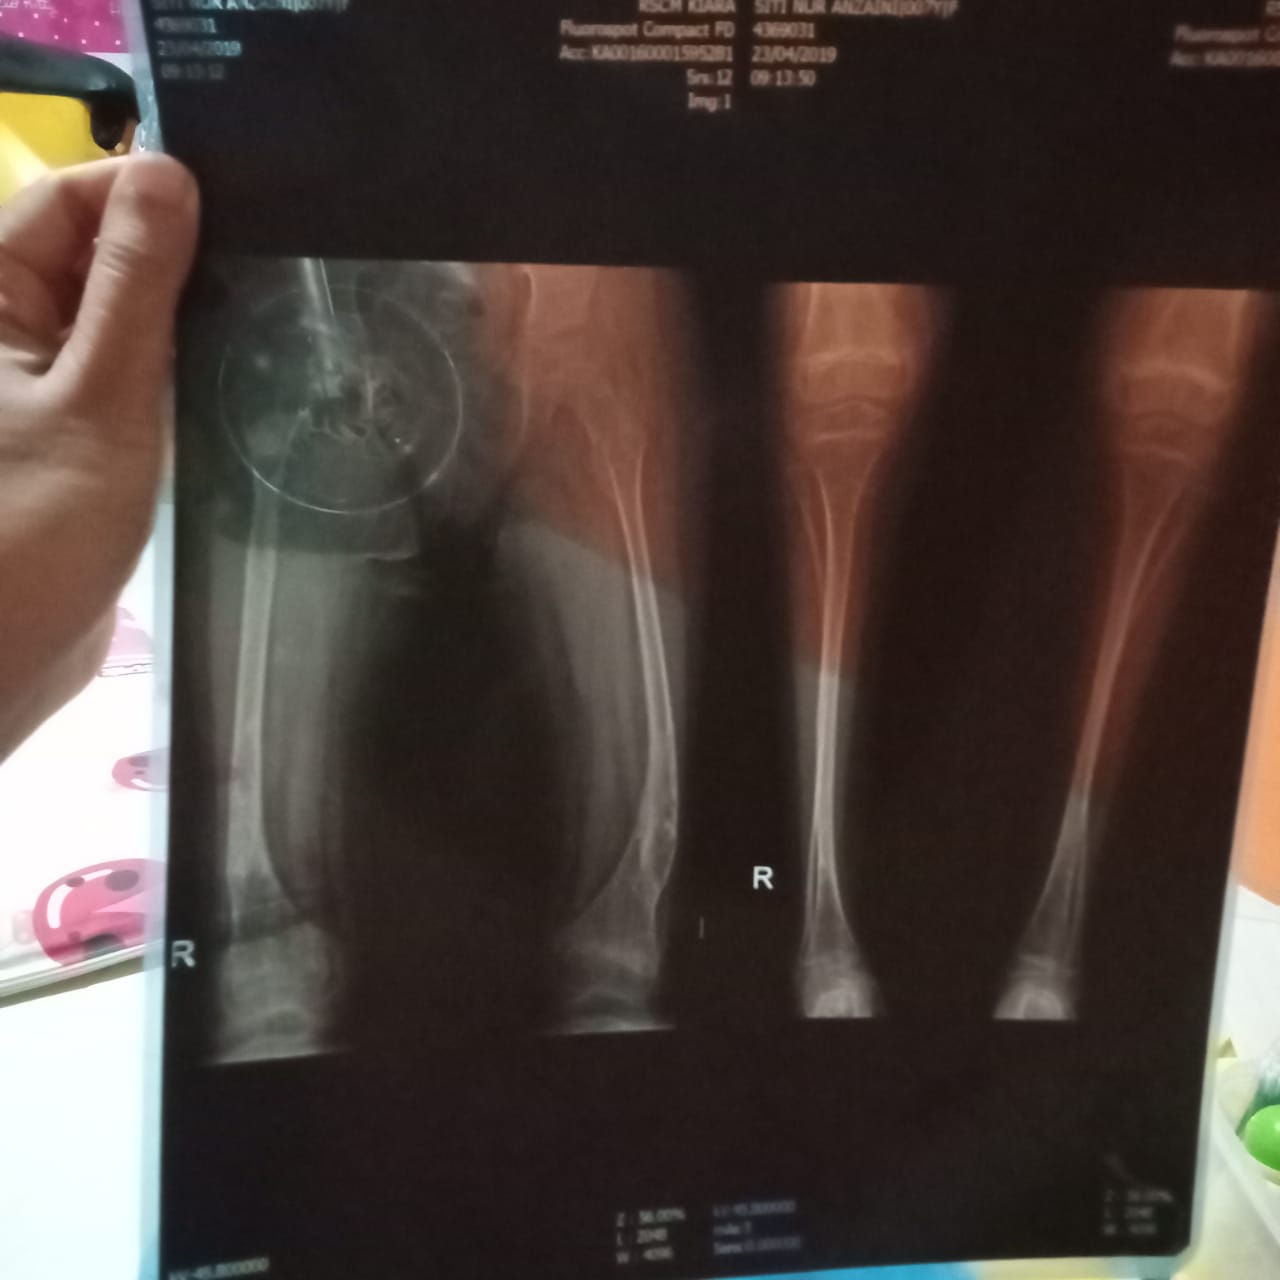

Setelah itu, pada tanggal 23 Februari 2023, Anza kontrol ke poli orthopedi di RSCM dan dilakukan pemeriksaan radiologi bone survey. Hasilnya akan keluar pada tanggal 2 Maret 2023 mendatang, dan dilanjutkan pemeriksaan ke poli pediatrik rehab medik pada tanggal 9 Maret 2023 untuk dirawat inap alendronate.

Pada tanggal 2 Maret 2023, anakku kontrol lagi ke poli orthopedi di RSCM untuk melihat hasil bone survey. Ternyata, ada bagian tulang yang masih belum menyatu. Maka dari itu, tim dokter melakukan tindakan pemasangan gips.

Setelah divonis osteogenesis imperfecta di usia 5 tahun, Anza dirujuk ke RSCM Jakarta. Sedihnya kami sebagai orang tua, dokter mengatakan penanganan untuk Anza sudah telat karena seharusnya ditangani lebih awal.